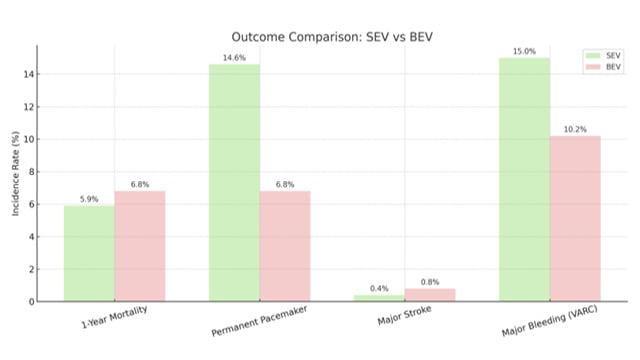

Featured research - TAVI: Predictive tools, AI innovation and reintervention strategies

17 Nov 2025 – From PCR London Valves 2025

This session presents cutting-edge research in TAVI, covering the development of predictive models for clinical valve thrombosis, comparative analyses between self-expandable and balloon-expandable valves from the Greek TAVI registry, and the emerging role of AI-guided Heart Team decisions. It also examines outcomes of reintervention strategies following...